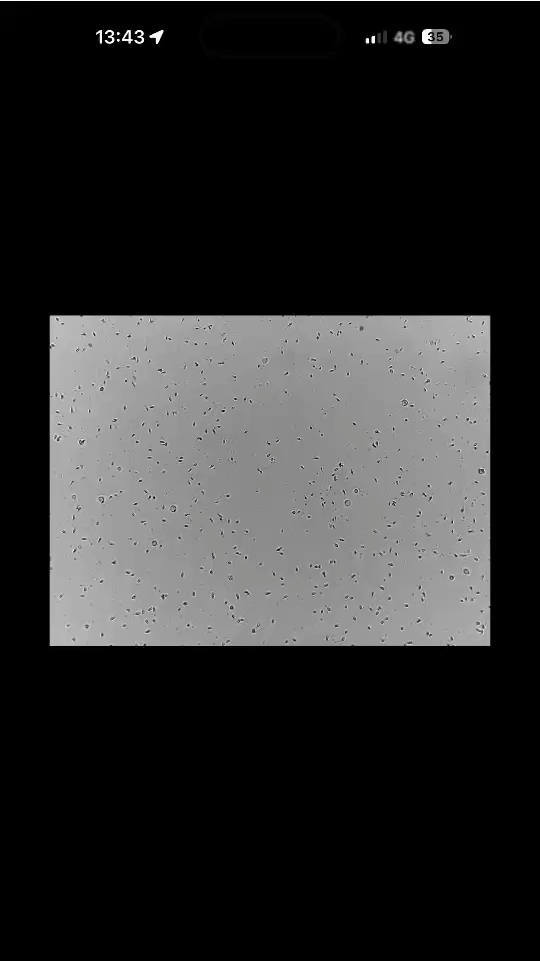

CASA(コンピュータ支援精液解析)による精液検査を導入しました。

CASA(コンピュータ支援精液解析)による精液検査について

CASAとは

CASA(Computer-Assisted-Semen-Analysis)とは顕微鏡+デジタルカメラ+コンピュータで精液所見を画像処理し、精子の「数」「形」「動き」「速さ」「進む方向」「停止」などを数値化します。

従来の目視では測定が難しかった精子の運動性・運動の質がより詳細に評価可能です。

CASAを用いた精液解析はタイミング法か人工授精かの選択や、体外受精か顕微授精へのステップアップにおける媒精法の選択に有用な判断材料となり、男性因子(精子側)での最適な治療方針を立てることに役立ちます。

実際にご自身でも精子の動画をスマホで見ることができます。